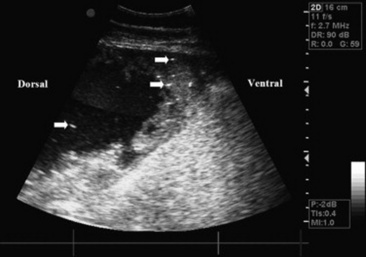

Ultrasonography

Thoracic ultrasonography, a companion to thoracic radiography, is useful for diagnostic, therapeutic, and prognostic evaluation of the extraparenchymal thorax, the pleural space, and the peripheral (superficial) parenchyma of the lung. Unlike thoracic radiography, in which specialized equipment is needed to image the adult large animal, thoracic ultrasonography is an imaging technique readily available to most practitioners. In many instances it is superior to thoracic radiography as an imaging method; examples include evaluation of pleural effusions, assessment of thoracic trauma, evaluation of neoplasms or granulomata, detection of mediastinal masses or abscesses, and guidance of transthoracic lung biopsy.9,10 Ultrasonography is considered greatly superior to thoracic radiography in the detection of rib fractures.11 This imaging technique should be considered for complete evaluation of any large animal with suspected or diagnosed pulmonary disease.

Although ultrasound waves will not penetrate the aerated portion of the lung, limiting the examination to extraparenchymal surfaces in normal horses, ultrasonography is superior to thoracic radiography in evaluation of these areas of the chest. Small amounts of pleural fluid that would be missed on auscultation, percussion, or thoracic radiographs can be detected, and the amount and character of pleural effusion in each hemithorax can be separately evaluated.9 Clear fluid is anechoic, but inflammatory cells, gas, and fibrin are echogenic, causing opacities that can be seen floating in pleural fluid and altering the general echogenicity of the fluid. Because of this, ultrasound is the method of choice for diagnosis and monitoring of pleural space disease. Ultrasonography should be used to guide catheter placement for drainage of accumulated fluid in the pleural space. The pleural surfaces are imaged well by ultrasound, with thickened or roughened areas easily detected. Lack of normal independent movement of the visceral and parietal pleural surfaces during the respiratory cycle, suggestive of adhesion formation, can be readily monitored.9,10

Consolidated lung is a better acoustic medium than aerated parenchyma and can be well visualized. If there is pleuropneumonia with consolidation or atelectasis caused by compression of the ventral lung by pleural effusion, it will be evident. Pulmonary abscesses or masses extending to the lung surface can be imaged, and ultrasound can be used for guidance for transthoracic biopsy.9,10 Thoracic radiography remains superior to ultrasound in diagnosis of pulmonary parenchymal disease and pneumothorax, but combined the two techniques will improve patient management diagnostically and therapeutically.